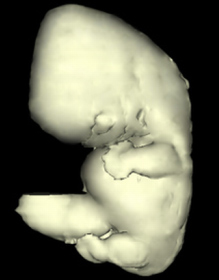

Carnegie Embryo #4430 | Location: 13-21

Source: The Virtual Human Embryo.